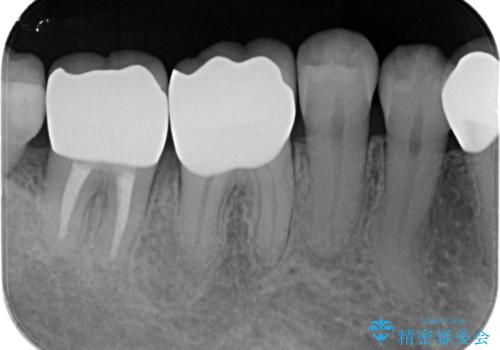

歯周ポケットの除去を併用したセラミック治療

- 歯周病や虫歯、歯の欠けなど多数の問題を他院で指摘され、今後長く持つように歯の問題をしっかりと解決したい。と希望され来院されました。

適合や審美性に優れるセラミック治療を行う前に、歯周病の問題を歯周外科を行うことで解決し将来的に不安のないような口腔内環境を整備していきます。

治療前に4-5mm程度あった歯周ポケットは全て2mm以内となり、非常に清掃性が高く、歯周病の再発しずらい環境に整えた上でのセラミック治療を実践することができました。